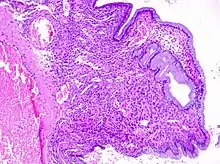

Histopathology of endocervical polyp: With endocervical epithelium and glands (mucinous columnar linings), edematous stroma and clear congestion. H&E stain.

Cervical polyps can be seen during a pelvic examination as cherry-red or greyish-white projections from the cervical canal.[2] Diagnosis can be confirmed by a cervical biopsy which will reveal the nature of the cells present.[3]